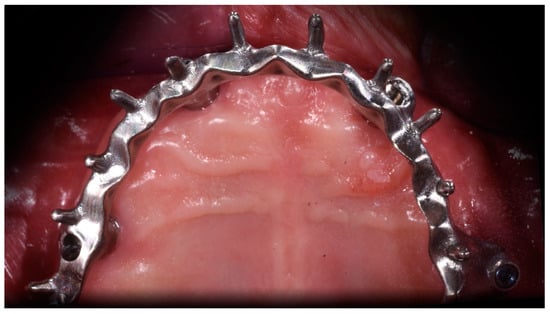

Angled Screwdriver Solutions and Low-Profile Attachments in Full Arch Rehabilitation with Divergent Implants

2. Report and Protocol